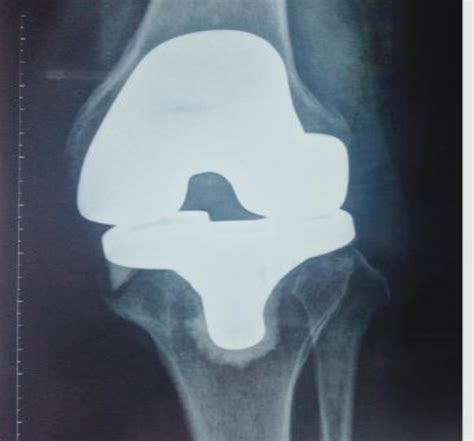

Total Knee Replacement (TKR) Dr A. Theodorides Knee Surgeon Specialist. Unwilling to accept restrictions, he discovered The Stone Clinic and Dr. It's time to look at what three months can bring in terms of healing and getting back.